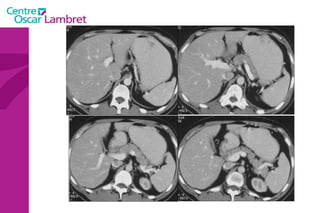

Adénopathies

Adénopathies Rétro-crurale inter-aortico-cave

Adénopathies Rétro-cave mésentériques vci

Adénopathies Adénopathies petite courbure